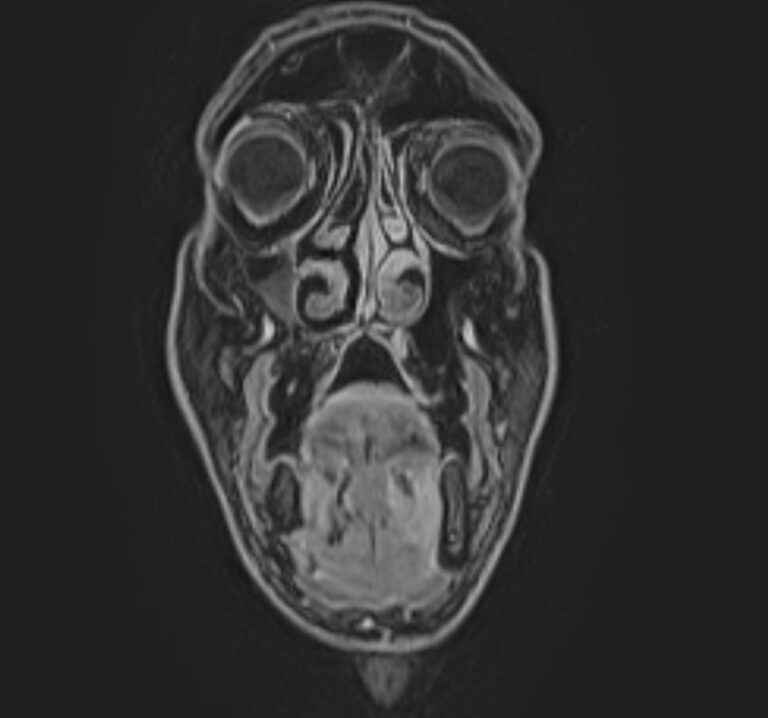

Магнитно-резонансная томография (МРТ) мягких тканей лица – это неинвазивное диагностическое исследование, которое использует магнитное поле и радиоволны для получения детализированных изображений структур мягких тканей в области лица. МРТ мягких тканей лица позволяет визуализировать мышцы, жир, нервы, сосуды и другие мягкотканные структуры, что помогает в диагностике различных заболеваний и патологий, таких как:

Перед проведением МРТ мягких тканей лица обычно требуется консультация врача, который определит необходимость и целесообразность исследования, а также даст рекомендации по подготовке. В некоторых случаях может понадобиться введение контрастного вещества для улучшения визуализации структур и выявления патологий.